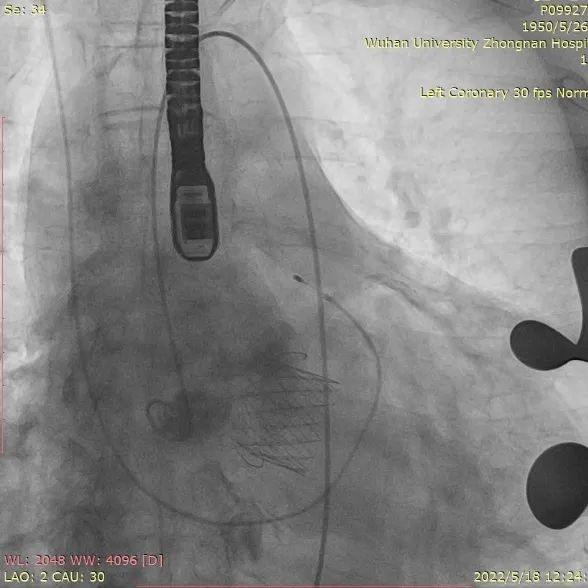

取平卧位,行右侧股动脉穿刺,置入6F鞘管,注入7000U肝素,分别送EBU3.75、EBU4.0、JL4指引导管均未能到达左冠口,EBU4.0塑型后成功达到左冠口,送VT导丝至前降支远端,送BMW导丝至回旋支远端,送2.0*20mm双导丝球囊于前降支近段狭窄处充分预扩张;送波科3.0*24mmDES一枚至前降支中段病变处,精准定位后释放,分别送3.5*16mm乳突球囊、3.0*15mmNC球囊至支架内修饰扩张。复查造影示支架膨胀良好,撤除鞘管,常规加压包扎,注意有无出血及高迷走反射。

冠造提示左冠前降支狭窄处

PCI后血流通畅